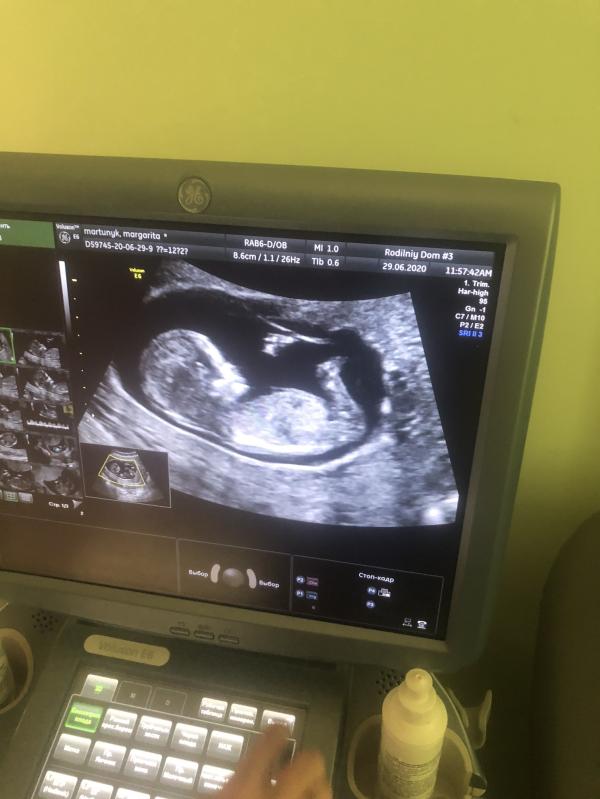

Моя 11, 12, 13 и 14 неделя беременности.

Обычно я очень спокойна, не паникую ни по какому поводу, но на 11 неделе начитавшись девочек в чате односрочниц их страхов, все это каким то образом перепало и на меня, я поняла что до сих пор не чувствую матку, так как при первой беременности я ее ощущала с самого начала, такой твёрдый шарик, а тут ничего. Помчалась я тогда сразу на узи, оказалось что все хорошо и матка была достаточно высоко, просто...